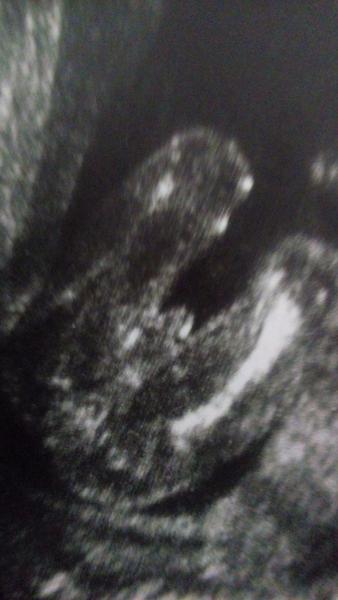

To vypadá na kluka ne? 🙂

@michalelka je to malinke, ale pokud dobre vidim, tak holka 🙂

@evulka2017 Řekla bych,že kluk 🙂

@evulka2017 kluk?

Kluk...holka má kávové zrnko

@evulka2017 taky bych tipla kluka

kluk